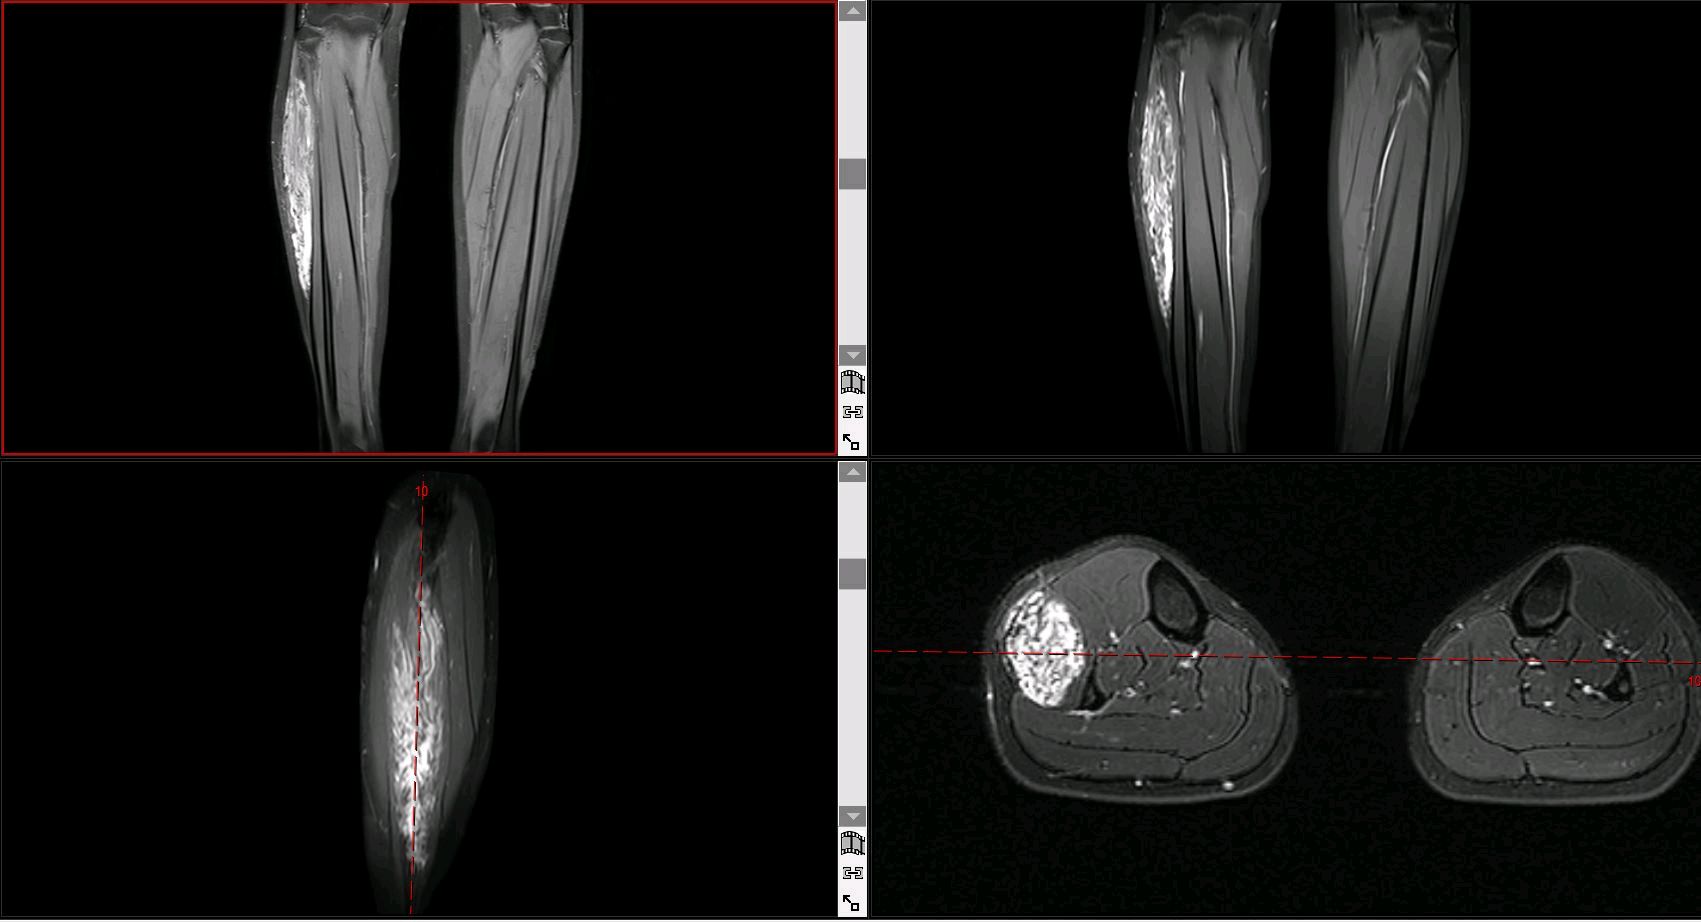

MRI:T1加权像呈不均匀高信号(脂肪成分),T2加权像显示混杂信号(纤维与血管成分)。

血管造影:可见异常静脉丛,但无动静脉瘘表现。